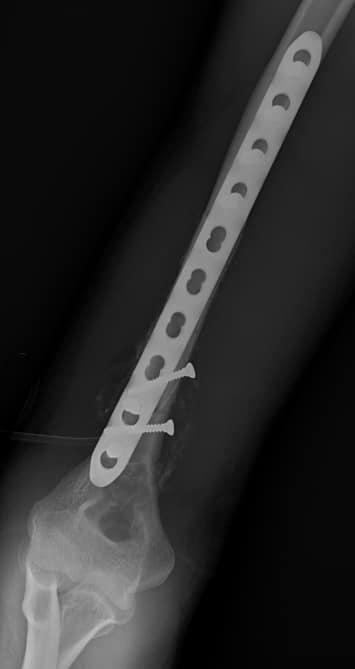

22歲男性,機車車禍。

由X光中可以看出明顯的遠端1/3的肱骨骨折,總共碎成了三大塊。

而這遠端1/3的肱骨骨折,在英文的稱呼中有專有的名詞: Holstein-Lewis fracture。

當然,最重要的是,在手術中須要小心的將橈神經從肌肉中抽絲剝繭的分離出來,檢查神經的完整性,最後打上鋼板。